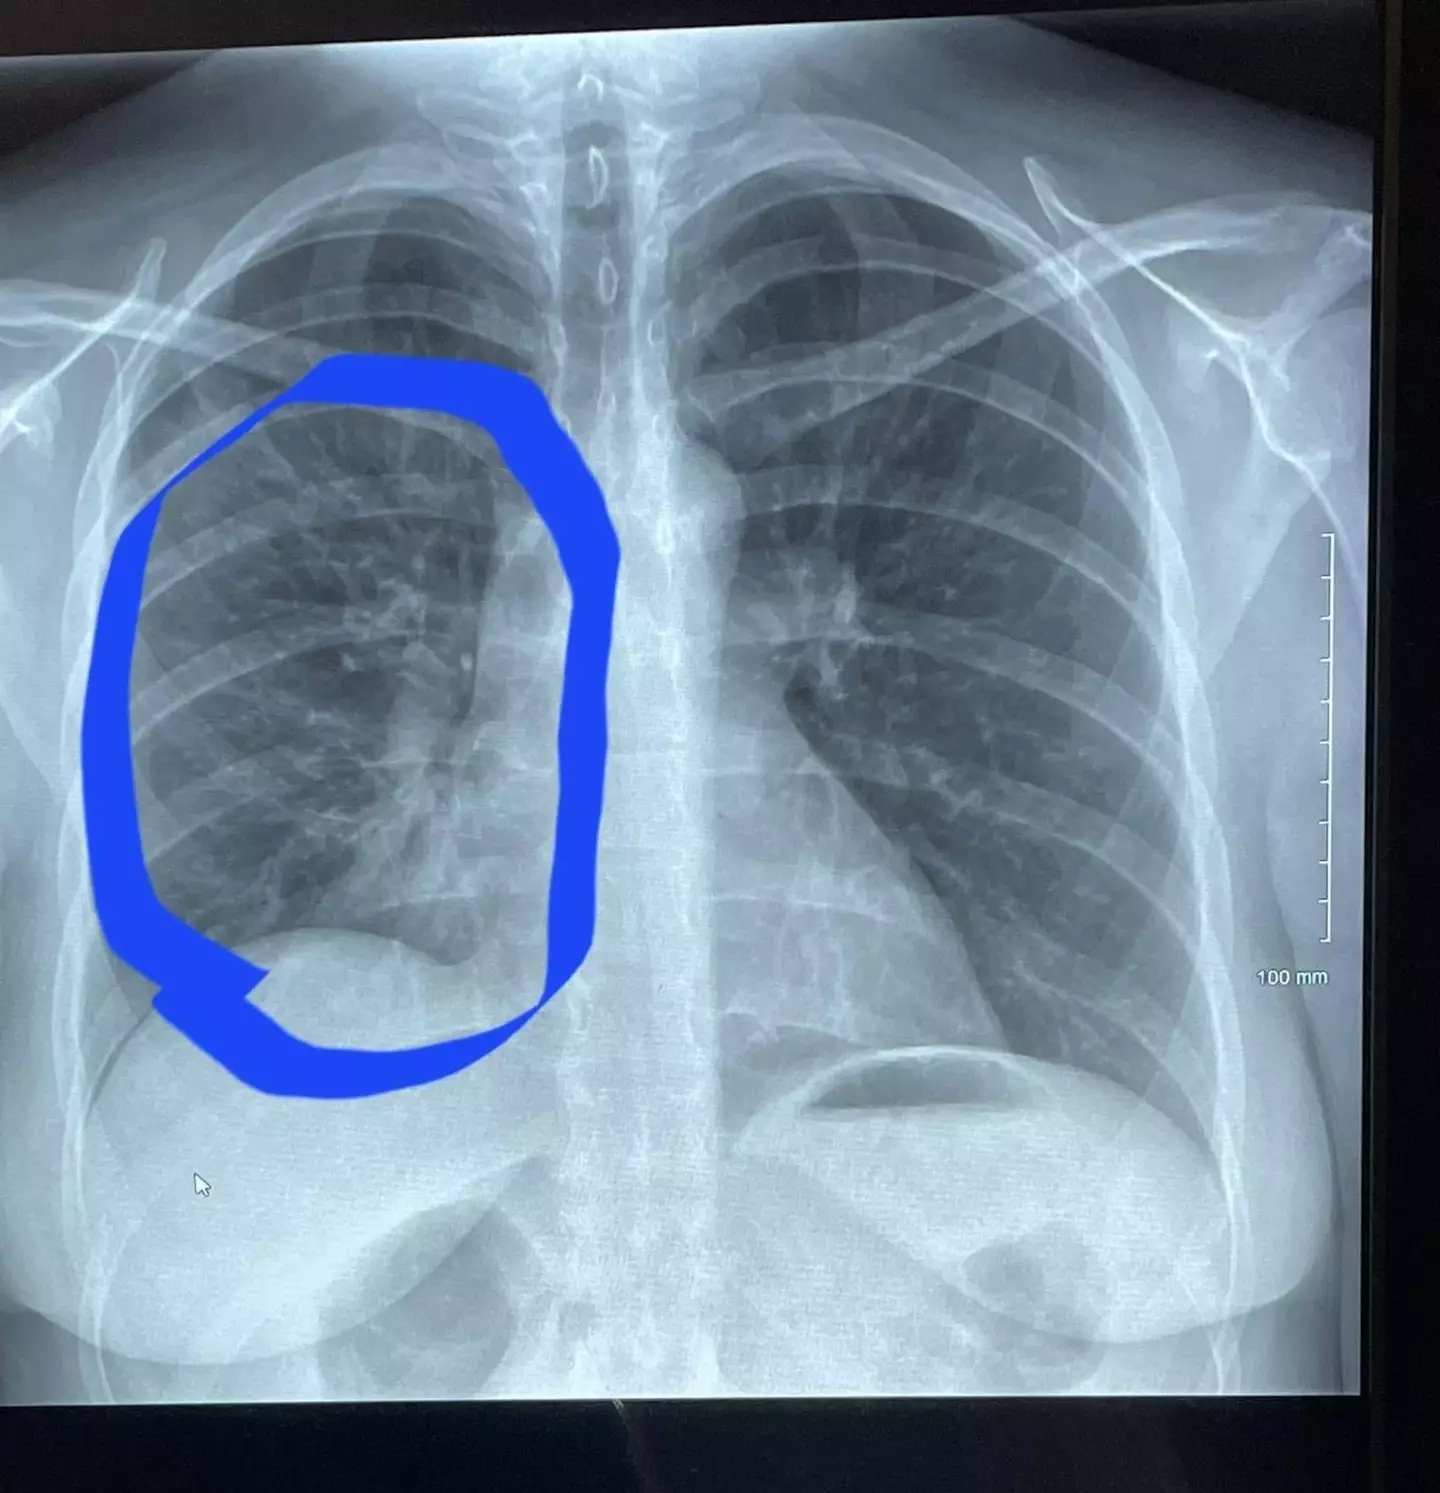

No departamento de emergência do hospital de Scott County, os médicos descobriram algo preocupante: uma obstrução em seu pulmão direito. “Disseram que era pneumonia. Parecia uma árvore com galhos, chamado ‘árvore em brotamento’, que é basicamente a deterioração do seu pulmão. Isso não deveria acontecer, a menos que você fosse um fumante pesado.”

Quando os médicos mostraram os exames de seus pulmões, Roth ficou chocada. “Pareciam os pulmões de alguém de 80 anos, alguém muito mais velho. Fiquei muito brava comigo mesma porque não tinha ideia de que o vape poderia fazer isso.”